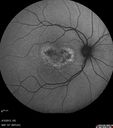

FUNDUS PHOTOGRAPHY - AUTO FLUORESCENCE: The image in the right eye does show some hyper auto fluorescence centrally and the left eye has hypo auto fluorescence centrally and there was some hyper auto fluorescence inferotemporally.

Asymptomatic Occult Subfoveal CNVM in Good Eye Visible on ICG790 views     (0 votes)

Asymptomatic Occult Subfoveal CNVM in Good Eye Visible on ICG548 views     (0 votes)